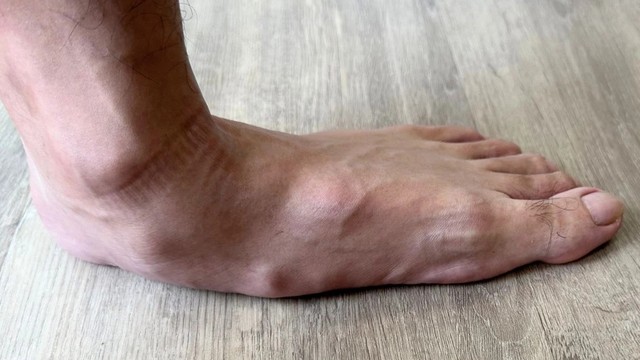

Bàn chân bẹt là tình trạng cấu trúc lòng bàn chân bị mất độ cong tự nhiên, khiến toàn bộ mặt dưới của bàn chân tiếp xúc với mặt đất khi đứng hoặc đi lại. Cùng nhà thuốc Long Châu xem hình ảnh bàn chân bẹt so với bàn chân bình thường để dễ dàng nhận biết dấu hiệu, giúp bạn phát hiện, xử lý sớm bàn chân bẹt.

Bàn chân bẹt là một tình trạng phổ biến ở trẻ em, do sự phát triển vòm bàn chân chưa đầy đủ, khiến chân chạm đất hoàn toàn. Cần có cách chữa bàn chân bẹt ở trẻ em để cha mẹ có thể kịp thời can thiệp đến sự phát triển vận động của trẻ. Dưới đây Nhà Thuốc Long Châu sẽ giới thiệu những phương pháp hiệu quả giúp cải thiện tình trạng này.

Bàn chân bẹt là tình trạng bất thường ở bàn chân và có thể gây ảnh hưởng nghiêm trọng đến sinh hoạt hàng ngày của người bệnh. Bàn chân dẹt có thể xảy ra ở trẻ em và cả người trưởng thành. Cách chữa bàn chân bẹt ở người lớn như thế nào?